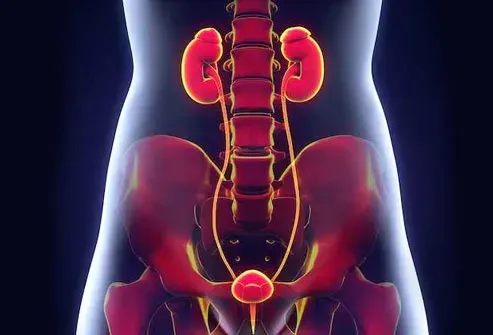

Infezione del tratto urinario

È la causa più comune di pipì frequente. I batteri infettano la vescica dei reni o i tubi che li collegano tra loro e al mondo esterno. La vescica si gonfia e non può contenere più urina che può essere nuvolosa sanguinosa o strana. Potresti anche avere nausea e dolore alla febbre nella tua parte o alla pancia inferiore. Il medico probabilmente prescriverà antibiotici per sbarazzarsi dell'infezione.